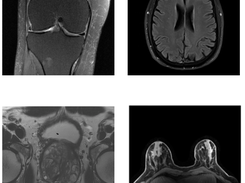

fastMRI is a large-scale collaborative research project by Facebook AI Research (FAIR) and NYU Langone Health that explores how deep learning can accelerate magnetic resonance imaging (MRI) acquisition without compromising image quality. By enabling reconstruction of high-fidelity MR images from significantly fewer measurements, fastMRI aims to make MRI scanning faster, cheaper, and more accessible in clinical settings. The repository provides an open-source PyTorch framework with data loaders, subsampling utilities, reconstruction models, and evaluation metrics, supporting both research reproducibility and practical experimentation. It includes reference implementations for key MRI reconstruction architectures such as U-Net and Variational Networks (VarNet), along with example scripts for model training and evaluation using the PyTorch Lightning framework. The project also releases several fully anonymized public MRI datasets, including knee, brain, and prostate scans.

• Includes MRI datasets (knee, brain, prostate) with raw k-space and DICOM data